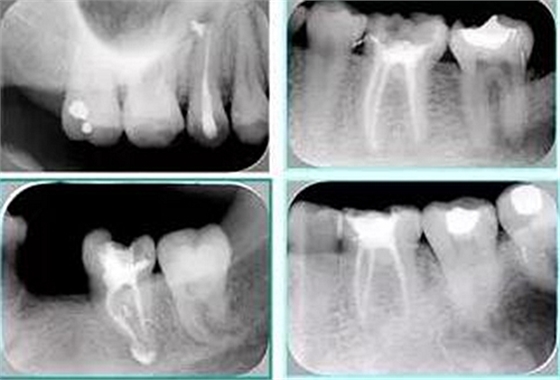

共有 4 張 X 線(xiàn)片,分別是術(shù)前、診斷絲 、主牙膠尖確認(rèn)、術(shù)后。

( 1 )術(shù)前:術(shù)前 X 線(xiàn)片用來(lái)了解牙齒的大概情況。術(shù)前預(yù)期為多根牙時(shí) X 線(xiàn)片應(yīng)偏頭拍攝。

( 2 )診斷絲:根據(jù)術(shù)前 X 線(xiàn)片進(jìn)行開(kāi)髓、根管的初步預(yù)備后,需要插入診斷絲,用來(lái)指示工作器械位置。常用 10 號(hào)或 15 號(hào)擴(kuò)大器作為診斷絲插入牙髓腔。

( 3 )主牙膠尖確認(rèn):通過(guò)術(shù)前預(yù)期和診斷絲診斷,明確工作長(zhǎng)度、牙根走向,進(jìn)行根管預(yù)備。之后應(yīng)進(jìn)行主牙膠尖(中銼)確認(rèn),已明確根管是否適合充填。

( 4 )術(shù)后:觀察治療效果。